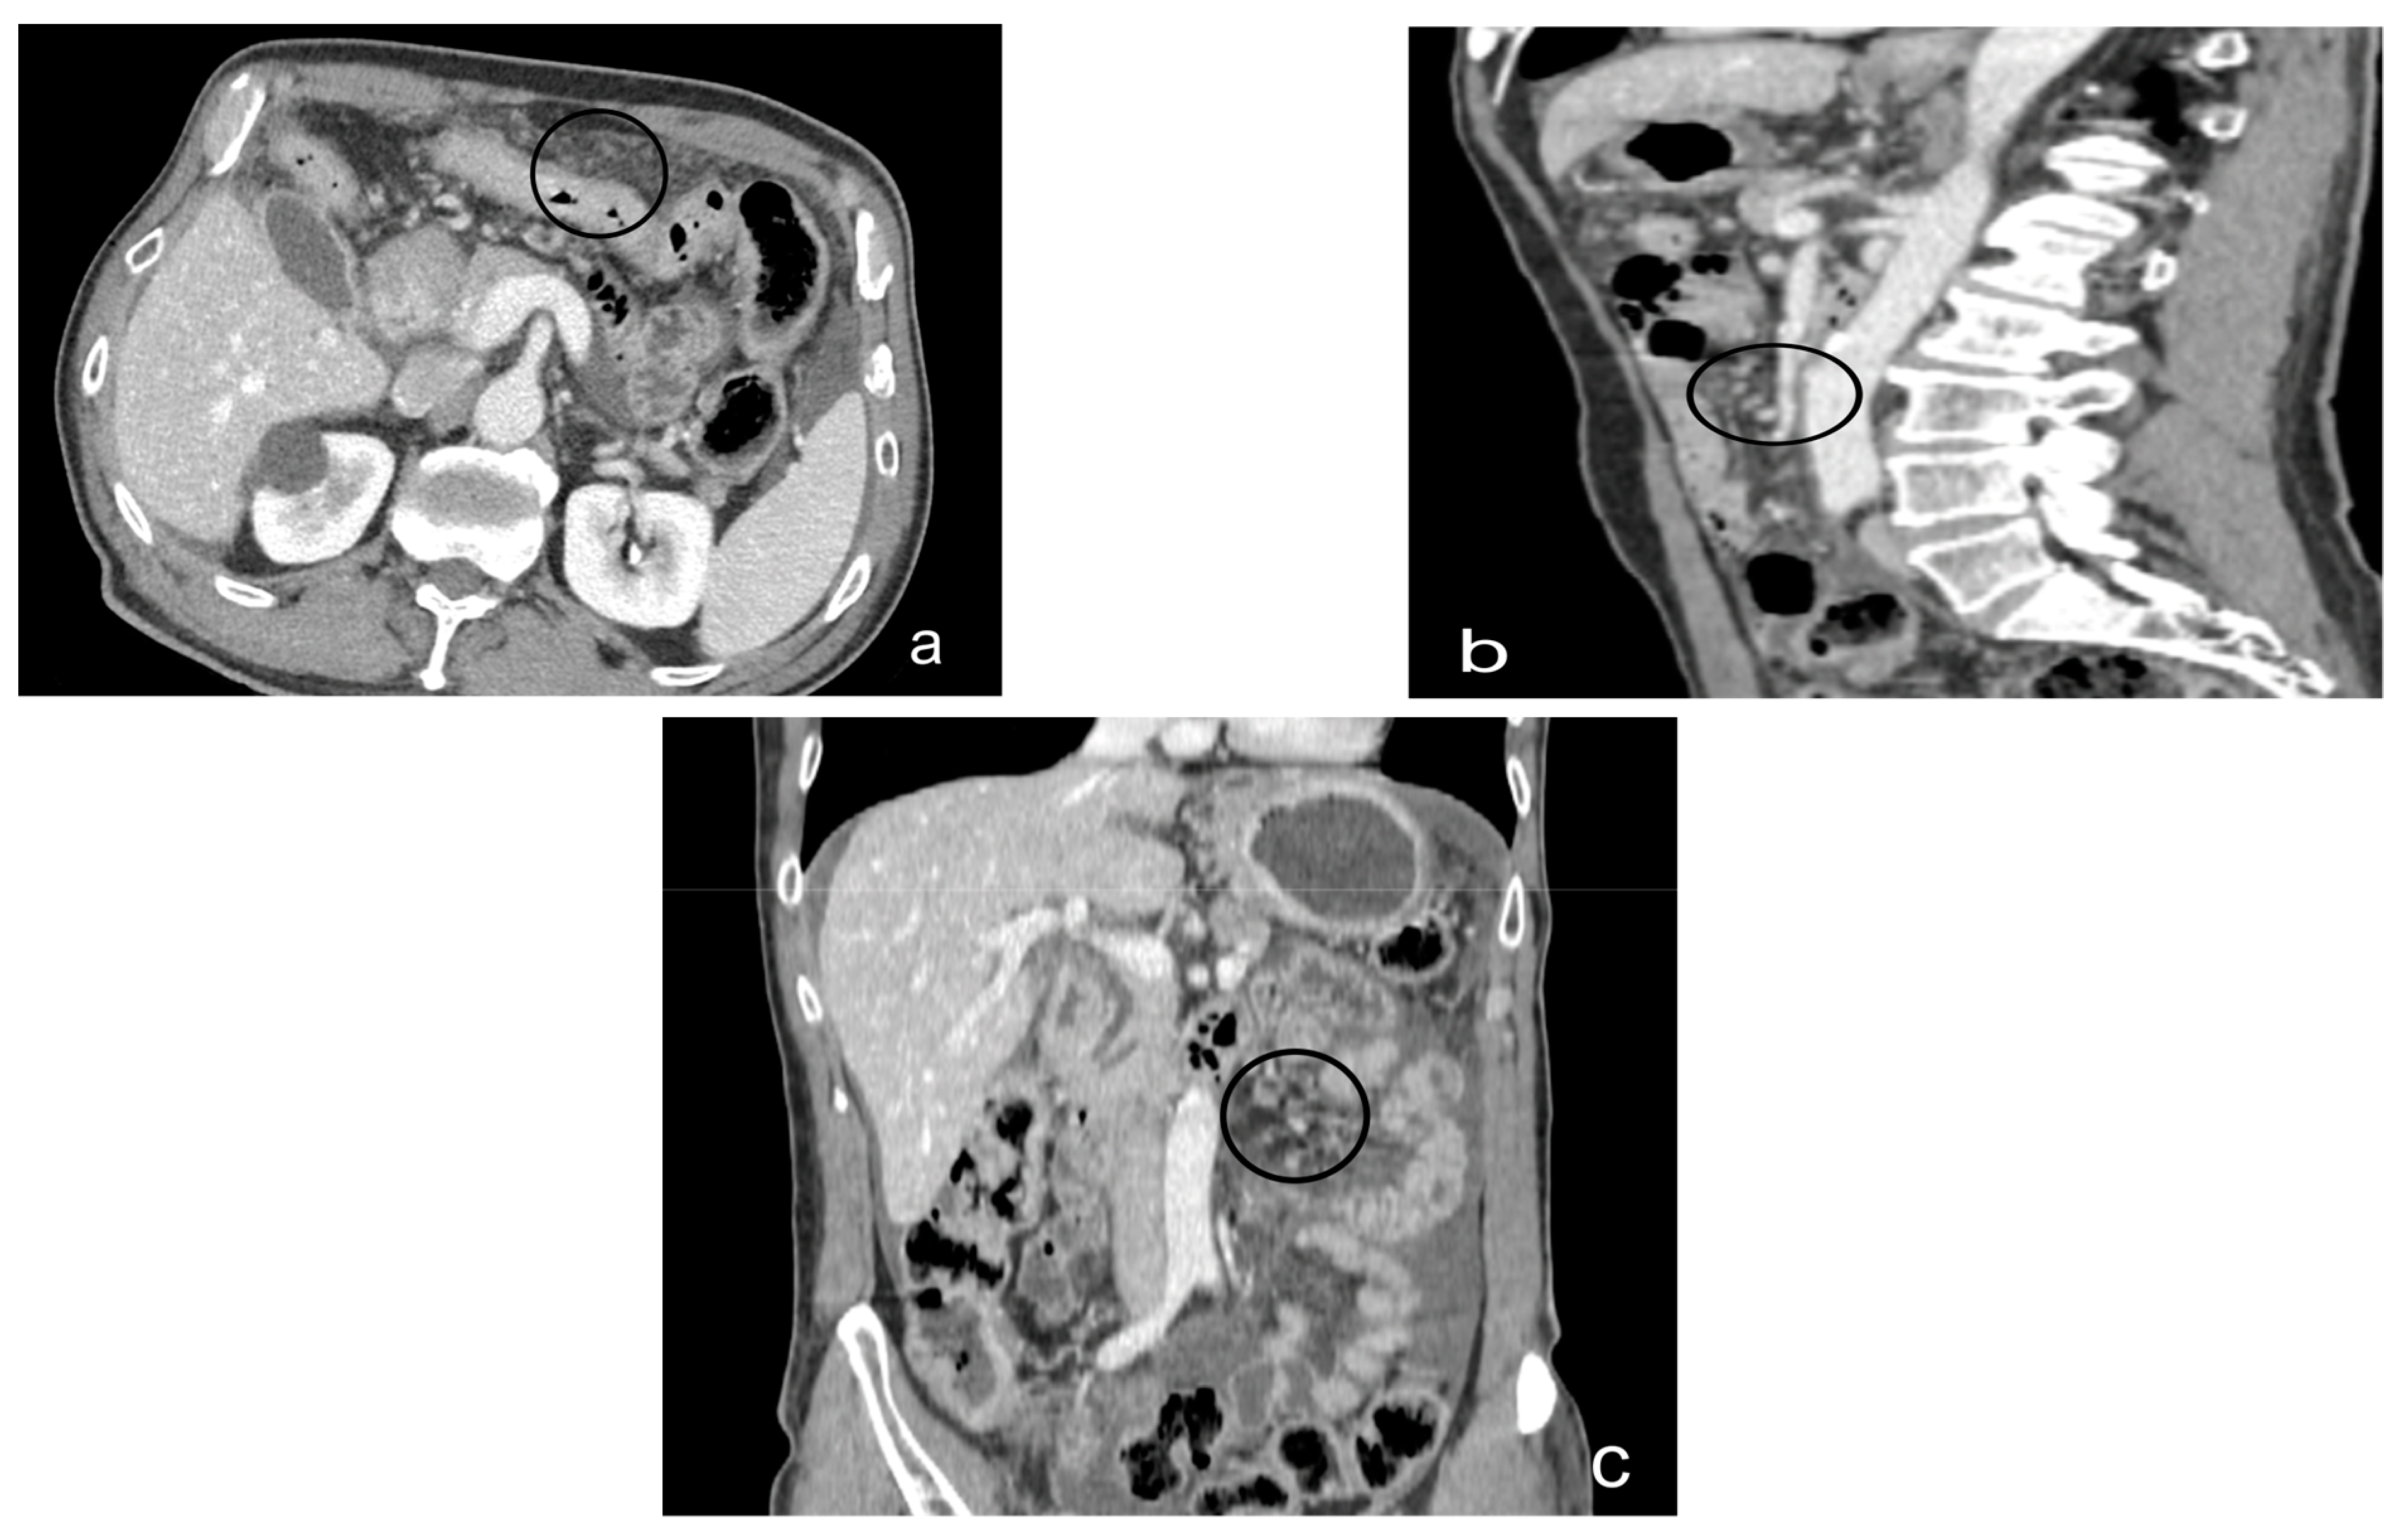

- Theca pattern: characterized by a nodular thickening of the visceral peritoneum lining the loops of the small bowel. Sometimes, this heteroplasic thickening generates narrowing, with the consequent obstruction and dilation of the proximal loops, a condition also referred to as “frozen pelvis” [95] (Figure 12).